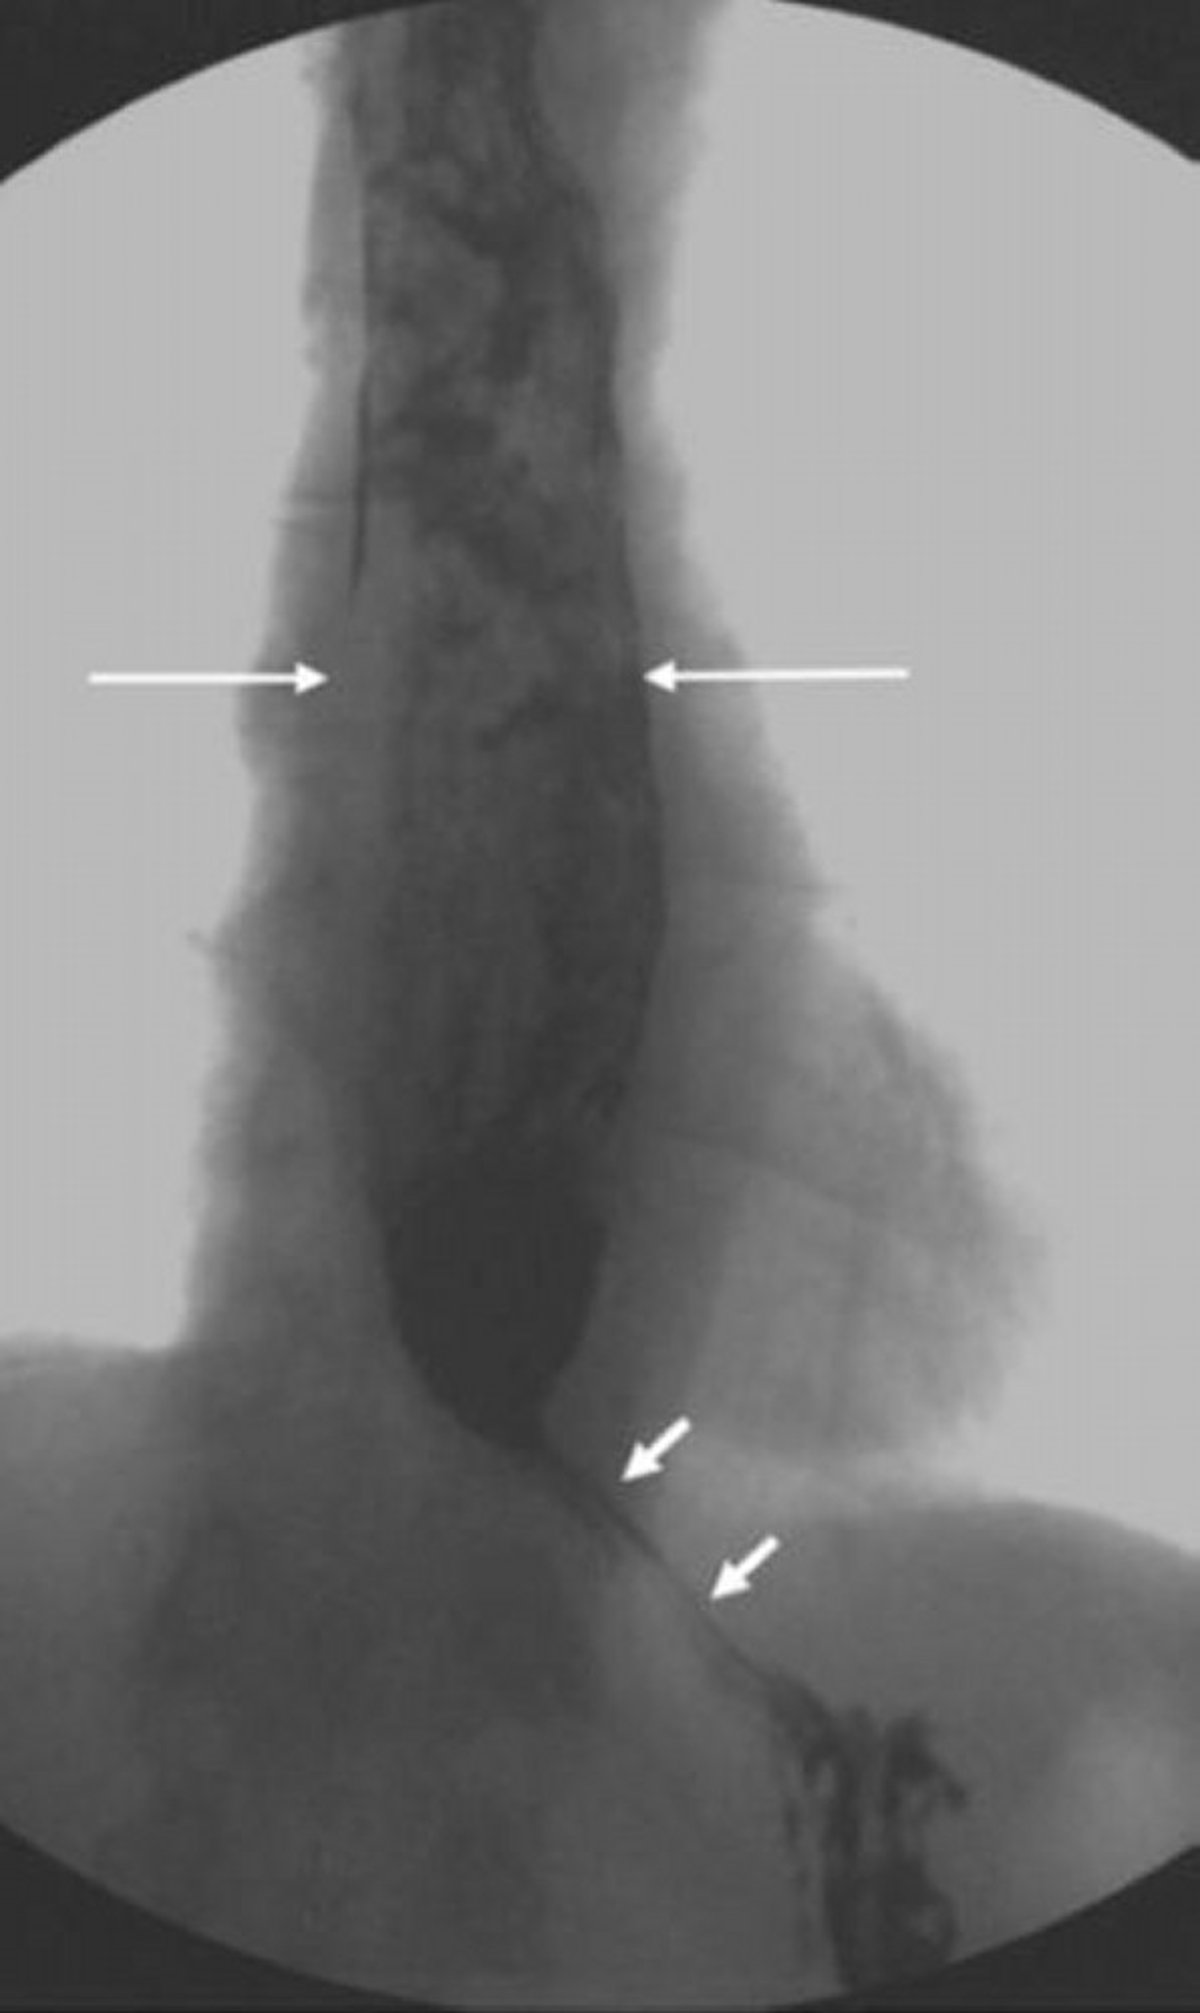

下部食道括約筋にくちばし状の狭小化を認める拡張した食道を示した食道造影像

この画像には,食道近位部が拡張して下部食道括約筋の弛緩が不完全になったアカラシアの病態が写し出されている。胃に通過しなかった未消化の食物により拡張した食道内に不均一な陰影(長い矢印)が認められるのに注目のこと。重度のアカラシアでは,くちばし状になった食道胃接合部(短い矢印)を通過できる造影剤の量がごくわずかとなる。